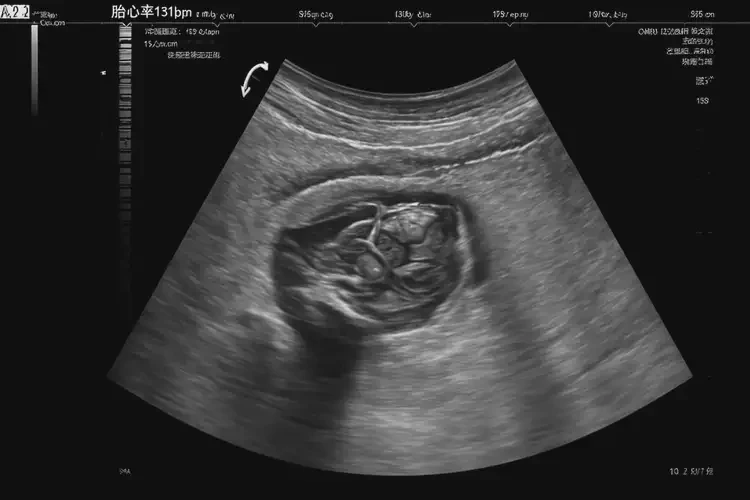

孕15周3天胎心131正常嗎

胎心131次/分鐘在孕15周3天屬于正常范圍。

胎心率是指胎兒心臟每分鐘跳動(dòng)的次數(shù),是評(píng)估胎兒健康狀況的重要指標(biāo)之一。在孕15周3天,胎兒的胎心率通常在120-160次/分鐘之間波動(dòng),因此131次/分鐘的胎心率在這個(gè)時(shí)期是正常的。